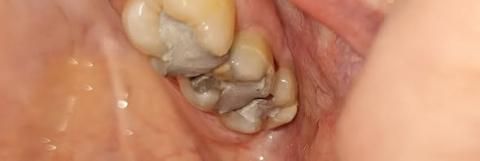

Case Type: Advanced Dental Caries and Calculus Accumulation

Full Analysis and Diagnosis

Upon examination, the posterior molars exhibit:

-

Extensive caries (tooth decay) on both left and right sides.

Possible pulp involvement — dark discoloration and cavity penetration indicate the decay may have reached the pulp chamber.